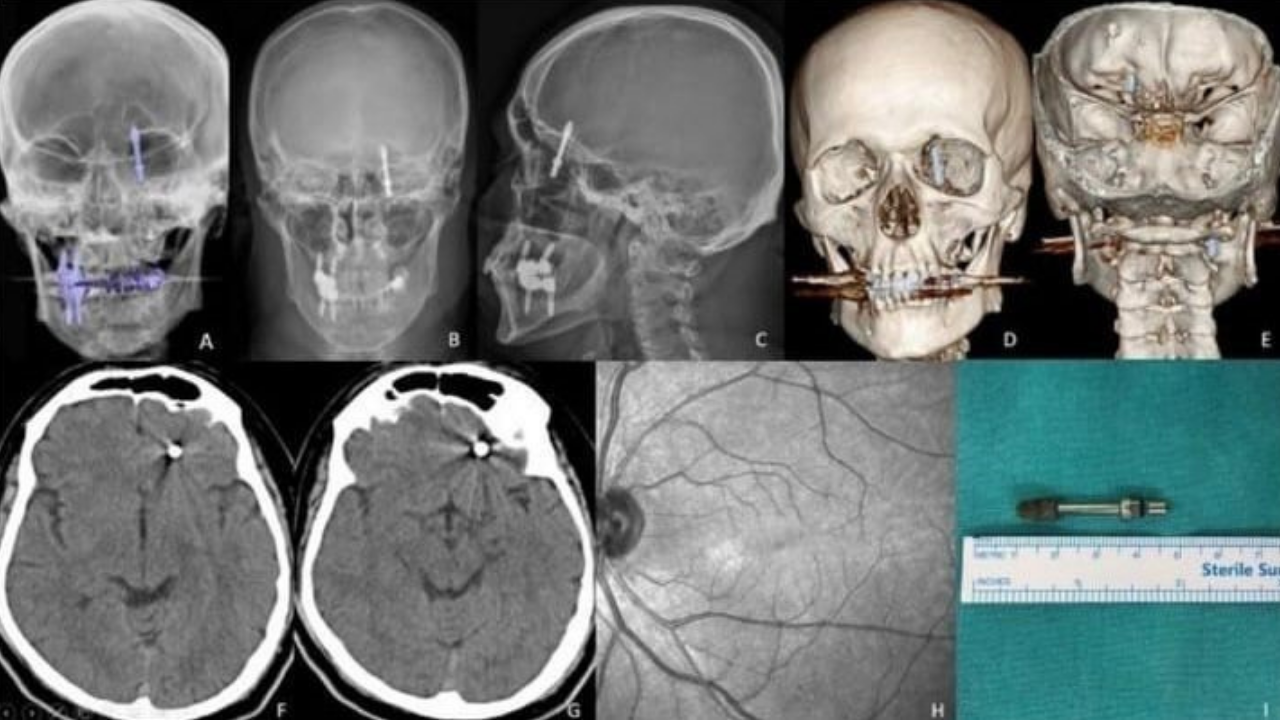

Nilüfer ilçesi. Diş tedavisi için gittiği özel klinikte yaptırdığı implant işlemi sonrası hayatı altüst olan Ramazan Yılmaz (40), iki yıldır adaletin yerini bulmasını bekliyor. İddiaya göre, diş hekimi A.D., tedavi sırasında yaptığı hatalı müdahaleyle implant vidasını çene kemiğini delip kafatasına kadar ilerletti.

Baygınlık geçiren Yılmaz, kliniğin kendi aracıyla hastaneye kaldırıldı. Tomografide vidanın beynine kadar saplandığı tespit edildi. Acil olarak ameliyata alınan Yılmaz, saatler süren operasyonla ölümden döndü.